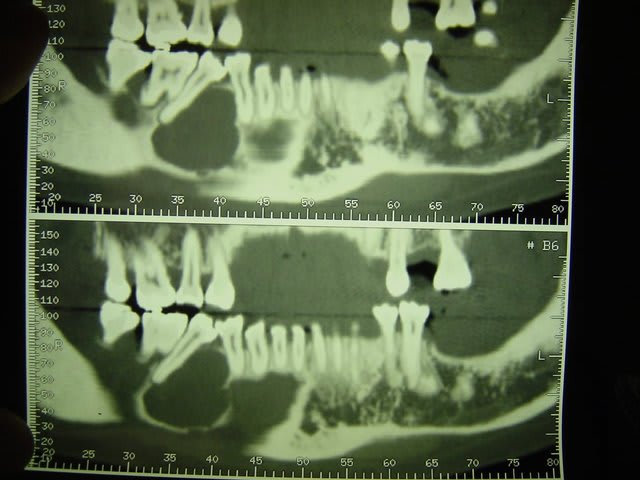

si tu regarde le scanner tu verras que le foramen mentonnier a ete completement repousse au niveau du rebord basilaire par le kyste (desole je ne sai plu quelle numero de photo )

j'ai pu donc realiser un lambeau de pleine epaisseur de 43 a 47 avec incision de decharge en mesial de 43 puis arrive au niveau du rebor basilaire j'ai disseque en epaisseur partiel.

au niveau du kyste j'ai decolle la membrane kystique en mesial distal lingual vestibulair emais pas en apical puis avec une pince hemostaqtiue tu tires doucement et il veint en un gros morceau .

ensuite tu as un acces visuel sufisant pour te permettre de nettoyer la partie apical en respectant le nerf alveolaire